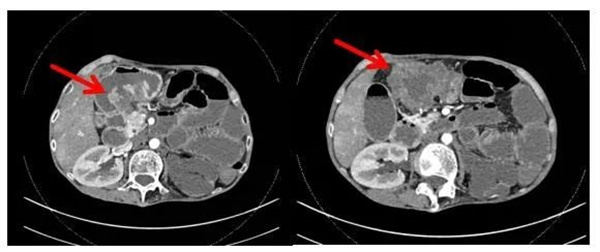

入院后,普通外科主任陈剑辉教授详细询问患者病史,同时完善相关检查,全腹CT显示横结肠占位性病变,考虑横结肠癌可能,并累及胃窦部、第2组小肠及结肠肝曲,其中部分与胃窦部相通,周围还伴淋巴结肿大及局部腹膜炎形成,有继发肠梗阻的迹象。